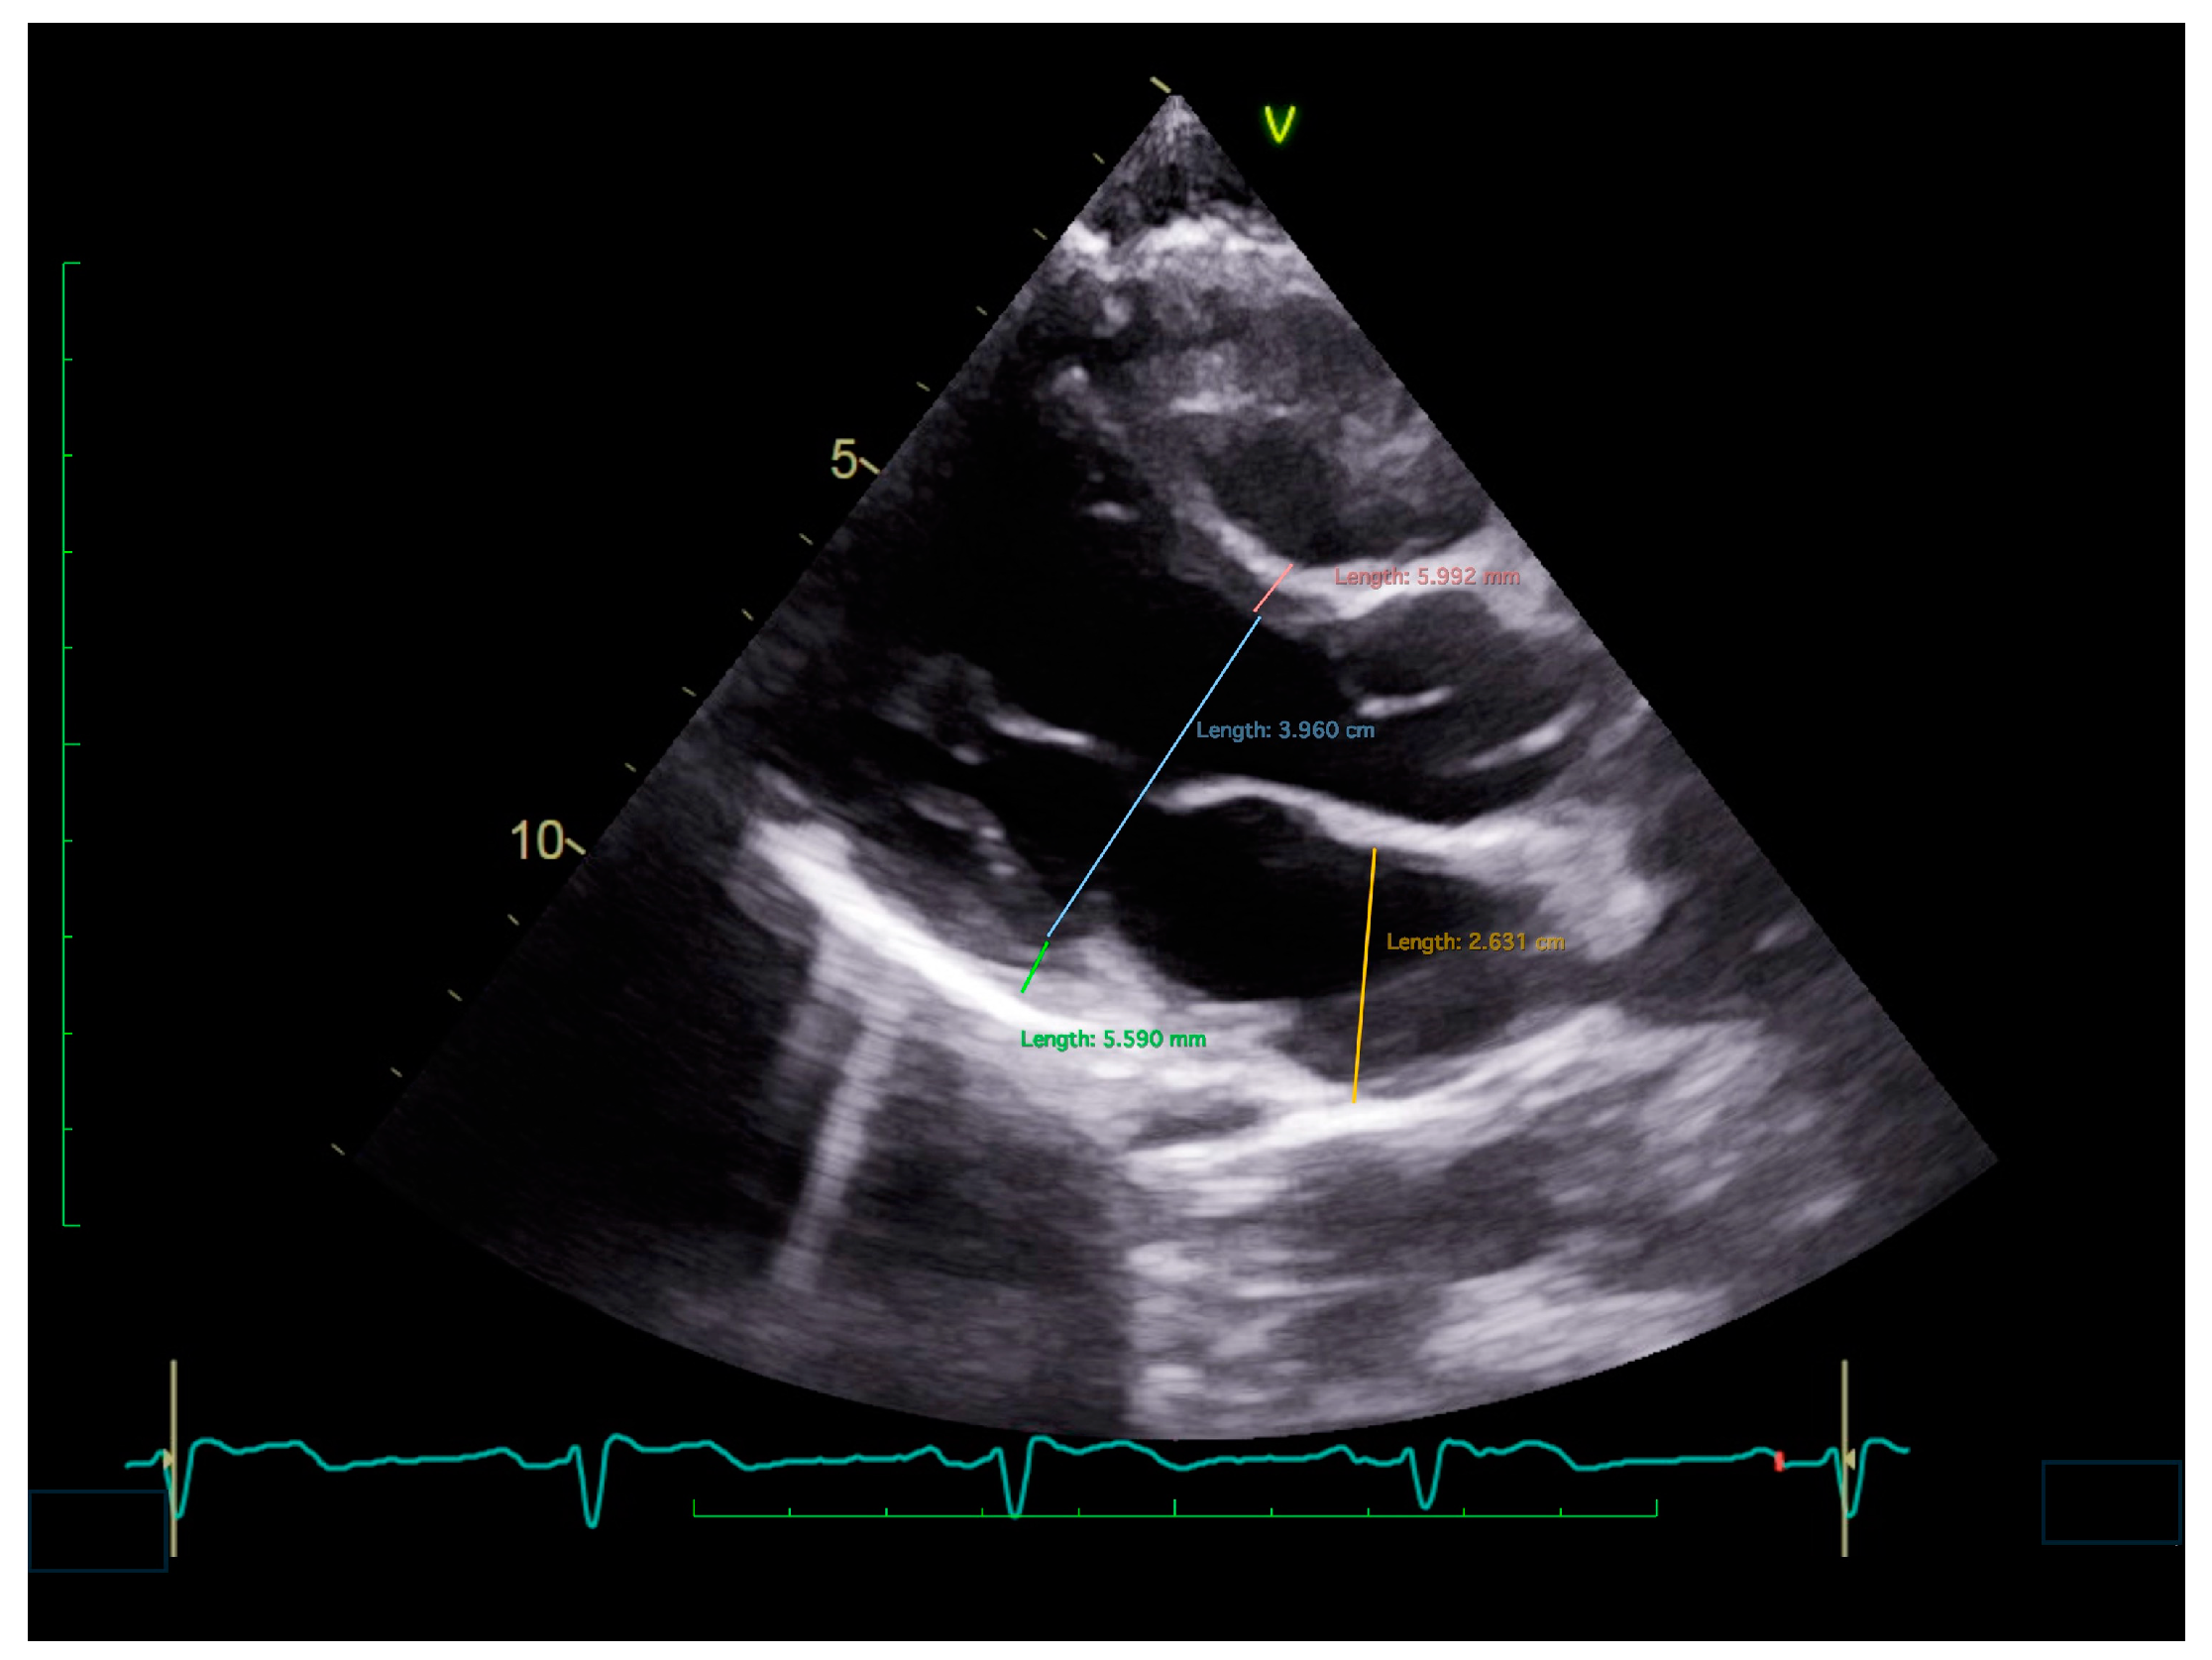

3.1. Exploring Geometry and Function of the LV in Patients with RS

3.2. From Syncope to Small Heart and Chronic Fatigue Syndrome

4. Left Atrium Geometry and Function in Patients with RS